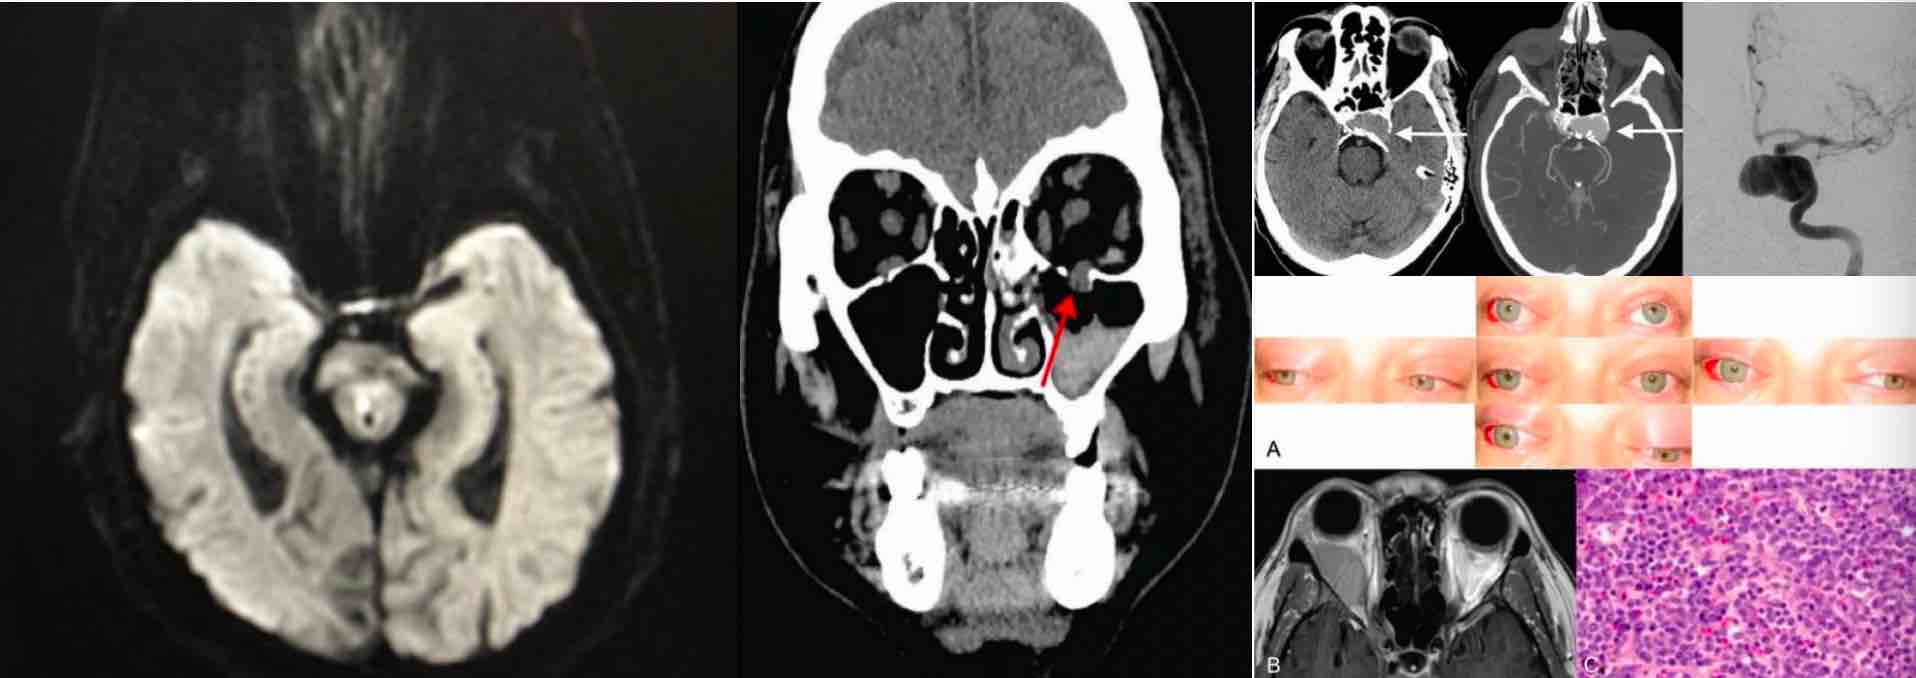

1、视神经脊髓炎(早期只是视神经炎或脊髓炎) 2、多发性硬化(大脑、视神经、脊髓多灶、多时相) 3、单纯视神经炎 4、动脉瘤压迫眼动神经 5、眼动神经炎症 6、线粒体脑肌病 7、垂体瘤卒中 8、眼睑痉挛 9、炎性假瘤 10、重症肌无力 11、偏头痛 12、脑中风

甲亢的病因有很多种,其中约80%为Graves病(弥漫性毒性甲状腺肿)引起,其具体病因目前尚不明,但已知病理机制中最主要的原因就是存在针对甲状腺的自身抗体,此病属于器官特异性自身免疫疾病,由于其自身免疫的的机制,在疾病病程中,大量淋巴细胞在眼球后的侵润,眼眶后成纤维细胞大量分泌多糖和糖肽聚糖并在眼球后组织沉积,导致眼外肌和脂肪肿胀,最终引起突眼